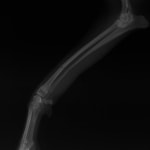

症例3:キルシュナーワイヤーのピンニングによる整復

ペルシャ猫 11ヶ月齢 雄

他院にて左大腿骨遠位の成長板骨折(salter-harrisⅠ型)が認められており、治療相談を目的として来院。当院にて、キルシュナーワイヤーを用いたピンニングにより骨折部位の整復を行いました。術後の経過は良好で、現在も経過観察中です。

術前レントゲン

術後レントゲン

Arthrex社のターゲティングデバイスを用いてピンニングの位置を調整することで、確実な固定を行っています。当院ではこの手術器具以外にも、人の手術にも使用される様々な器具を導入し、手術精度を高め、また医療メーカーと新しい器具の開発、試作にも取り組んでおります。